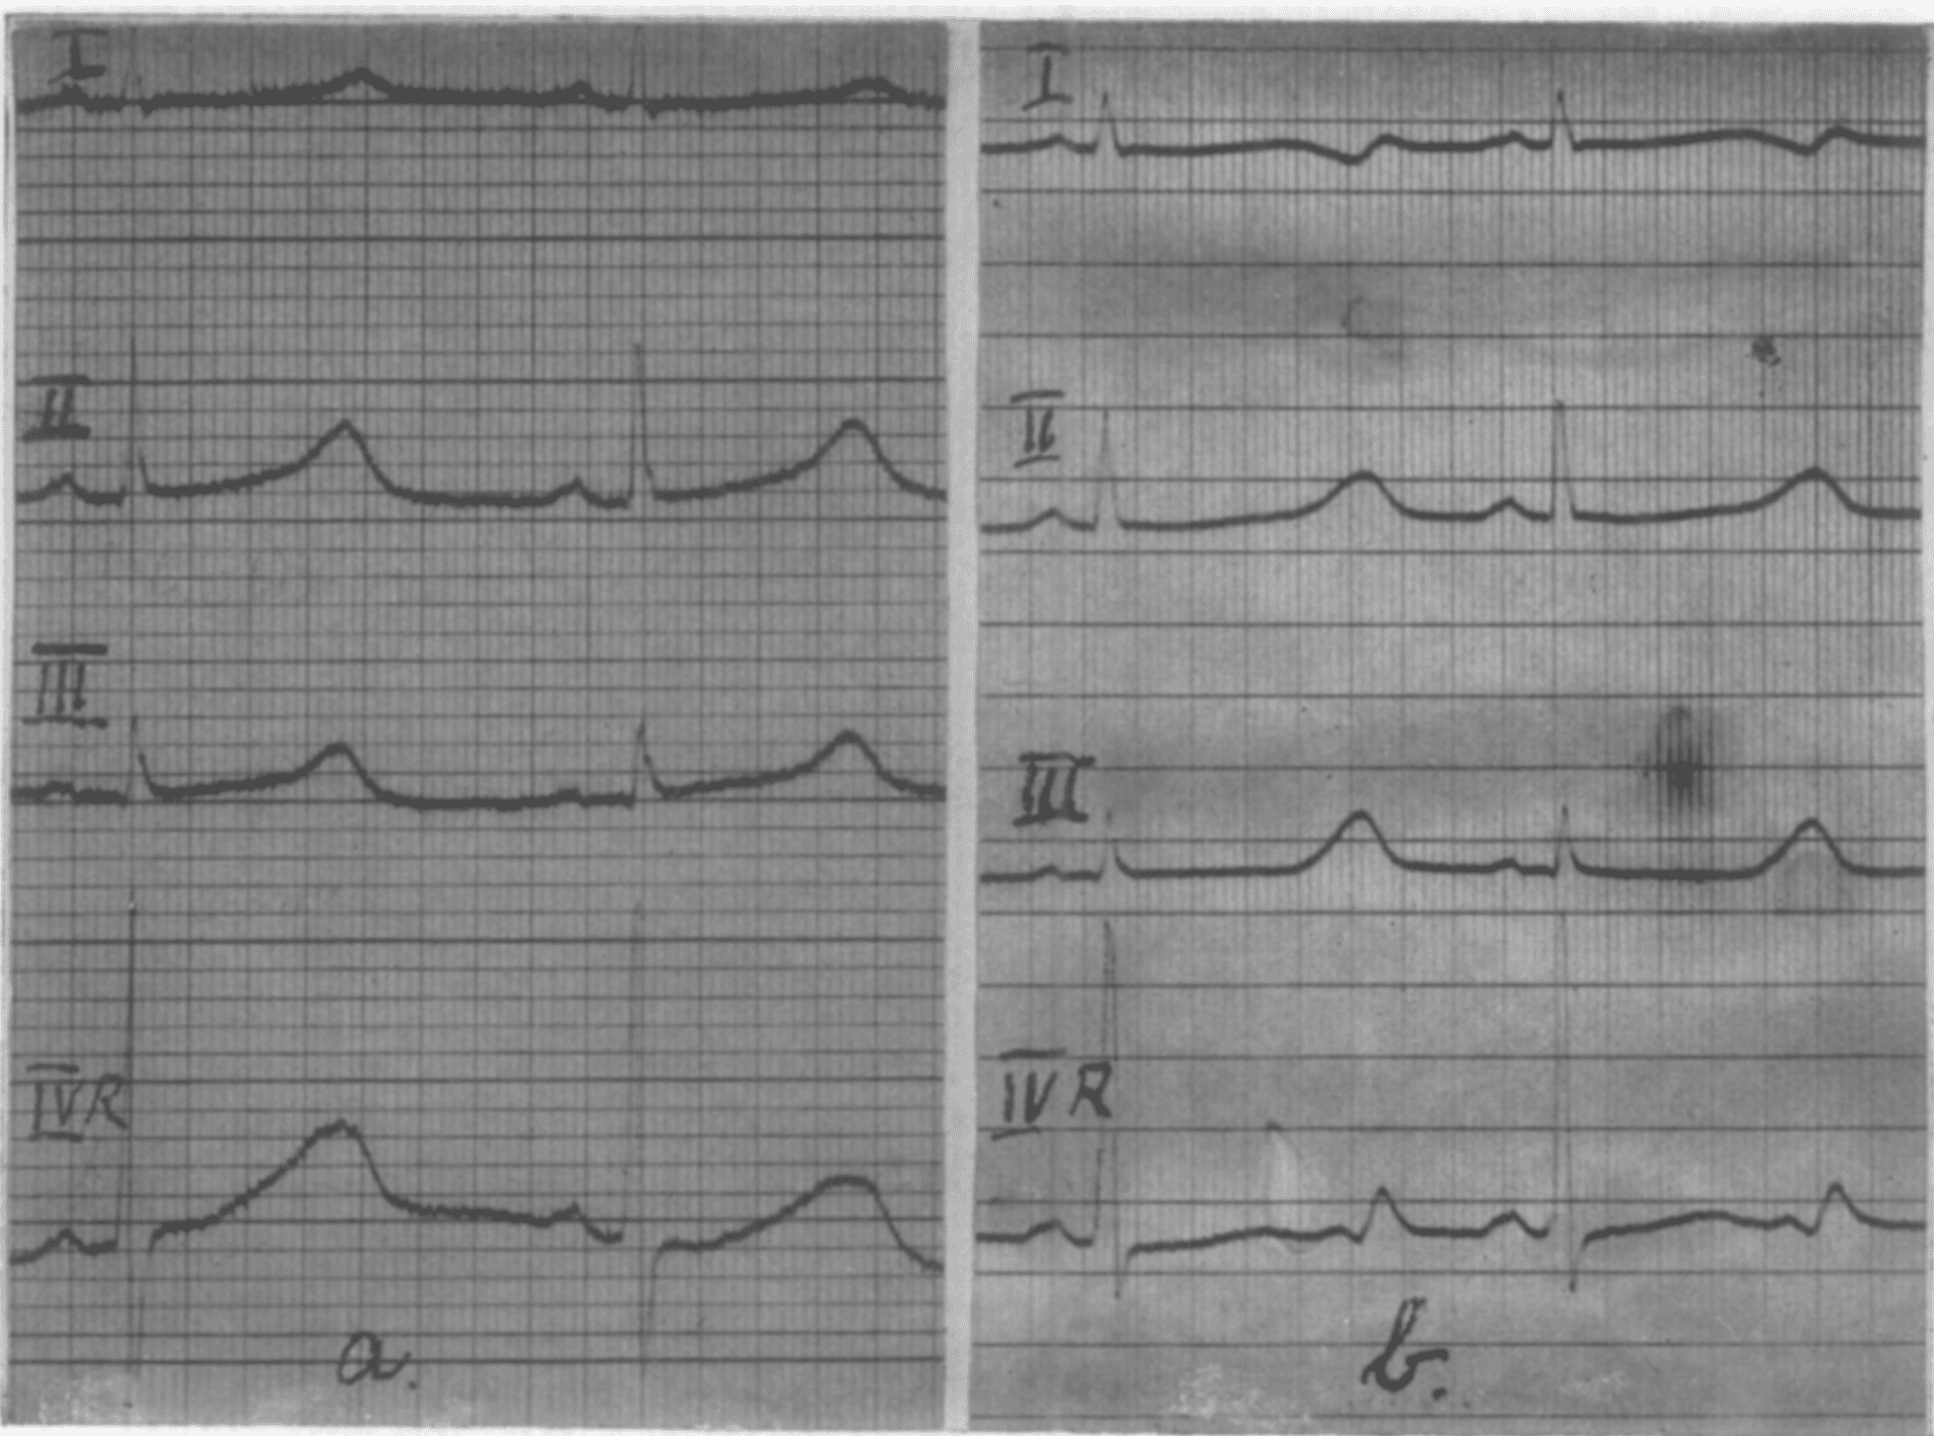

Jervell and Lange-Nielson recounted one case of a young boy, born in 1944 suffering from repeated ‘fainting attacks’ since the age of 3. The attacks usually occurred following effort. Occasionally the boy had complained of palpitations and precordial pains. In July, 1953, he was examined with the only pathologic finding being a prolongation of the Q-T interval in the electrocardiogram, worse following exercise. On Nov. 19, 1953, he had a further attack. He suddenly became pale and fell unconscious and died.

(a) ECG July 20. 1953, during rest. Leads I, II, III. IVR. Q-T = 0.50s. R-R = 0.88s.

(b) ECG July 20, 1953. after stair-running. Leads I. II. III, IVR. Q-T = 0.60s R-R = 0.86s. Jervell A, Lange-Nielsen F. 1957